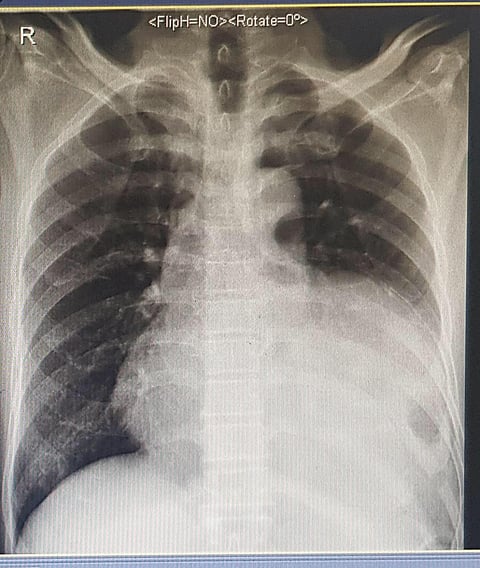

وأظهرت الكشوفات والأشعة أن المريض يعاني من فتق بعضلة الحجاب الحاجز من الجهة اليسرى، وأن جزءًا كبيرًا من الأمعاء دخلت في تجويف الصدر؛ مما سبب له انسدادًا معويًّا وقصورًا في التنفس بالرئة اليسرى.